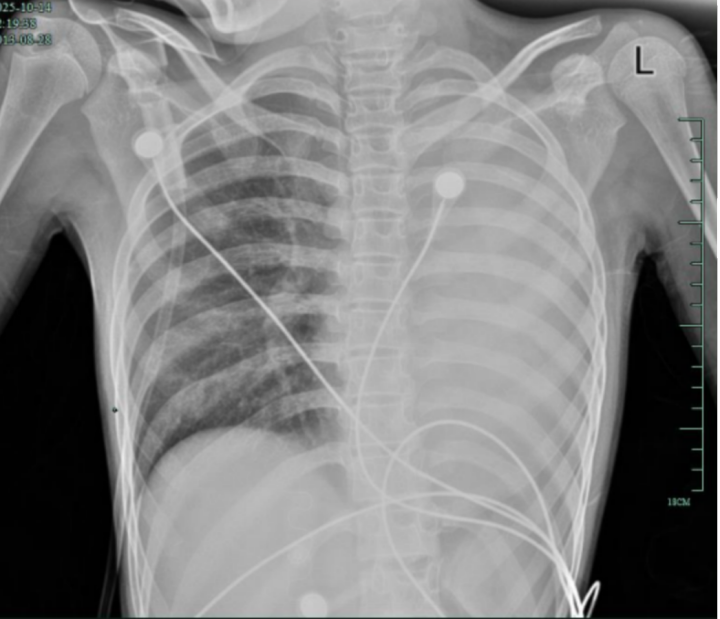

治疗后,“白肺”被吸收,心脏边缘清晰可见

值得高兴的是,笑笑的“白肺”基本吸收,恢复如常,没有留下严重的并发症。